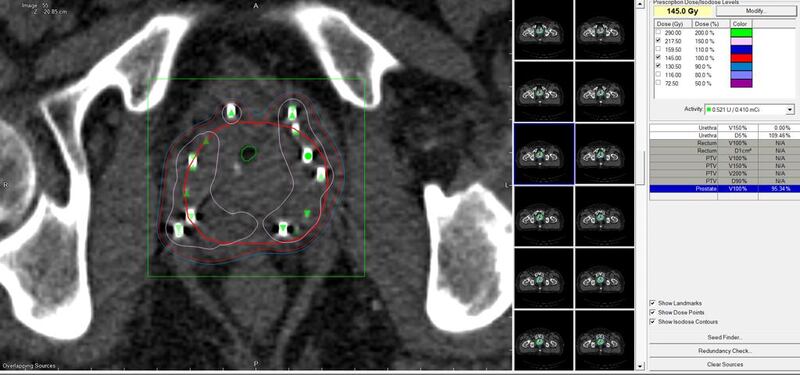

واستمرت العملية لساعتين غُرست خلالها 82 بذرة مُشعة في المريض وأجراها الدكتور نديم برفاز، استشاري أول علاج بالإشعاع بالمركز بوجود طاقم متخصص من أطباء العلاج الإشعاعي وأطباء التخدير والفيزيائيين الطبيين والممرضين.

وبيّن أنّ عملية زراعة البذور المشعة تقوم على غرس مصادر مشعة (بذور) في البروستات لتبعث جرعة منخفضة ومتواصلة من الإشعاع خلال فترة زمنية محددة، لتدمير خلايا البروستات وبذلك يتم القضاء على الخلايا السرطانية نهائيًّا، بينما تتجدد الخلايا السليمة وتعود إلى طبيعتها بسهولة مع مرور الأيام.